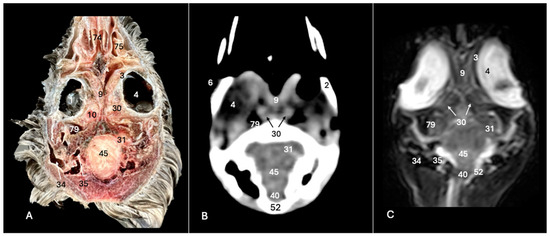

3.1. Anatomical Sections

3.2. Computed Tomography (CT)

3.3. Magnetic Resonance Imaging (MRI)